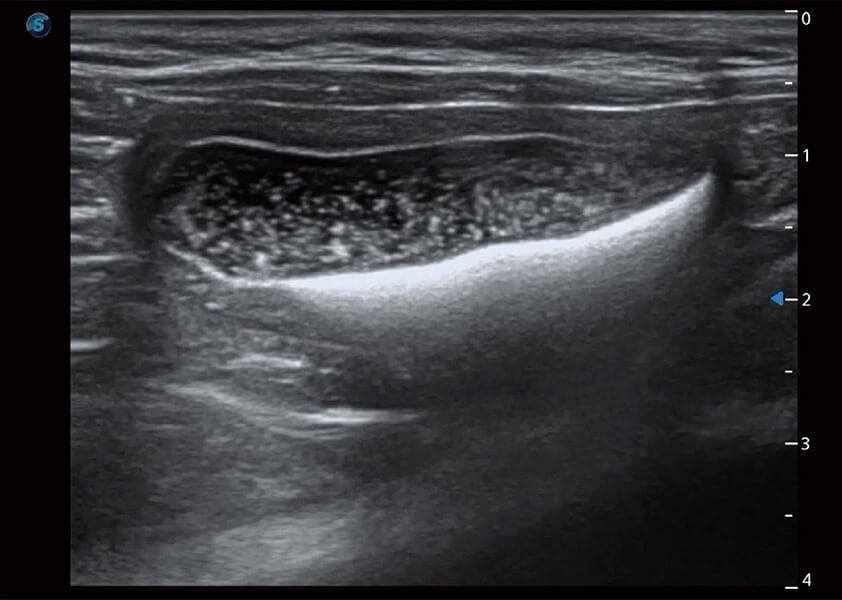

ProPet 60 作为一款高端台式动物超声设备,为动物医生的日常诊断提供了一系列贴合动物临床需求、解决临床实际问题的高级成像功能。凭借全系列高清探头,满足医生对腹部、心脏、生殖、浅表、肌骨等成像的所有需求,切实帮助您提升检查效率,提高诊断信心。

动物是人类最亲密的朋友和最值得信赖的伙伴。乐玩lewin国际也一直致力于探索动物专用的超声影像解决方案。 全新推出的ProPet系列,是乐玩lewin国际在动物超声影像智能化、专业化、精准化的一次跨越式革新。动物不能用言语来表述自己的不适,通过超声影像,ProPet系列搭建了动物医生与不同物种沟通的“桥梁”,为动物医生注入了“治愈之力”。